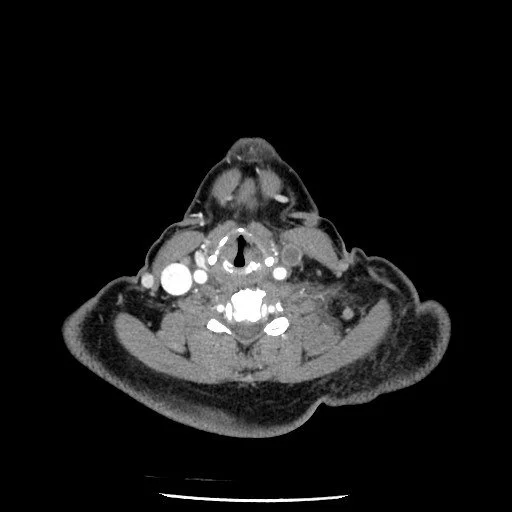

Lemierre Syndrome

• Thrombophlebitis of internal jugular vein secondary to bacterial infection typically from pharyngitis

• Presents few days after pharyngitis with trismus

• Can cause septic emboli and abscess formation

• >80% of cases associated with gram neg bacillus, usually Fusobacterium necrophorum

• Case courtesy of Safwat Mohammad Almoghazy, Radiopaedia.org, rID: 86127 (lemierre syndrome)